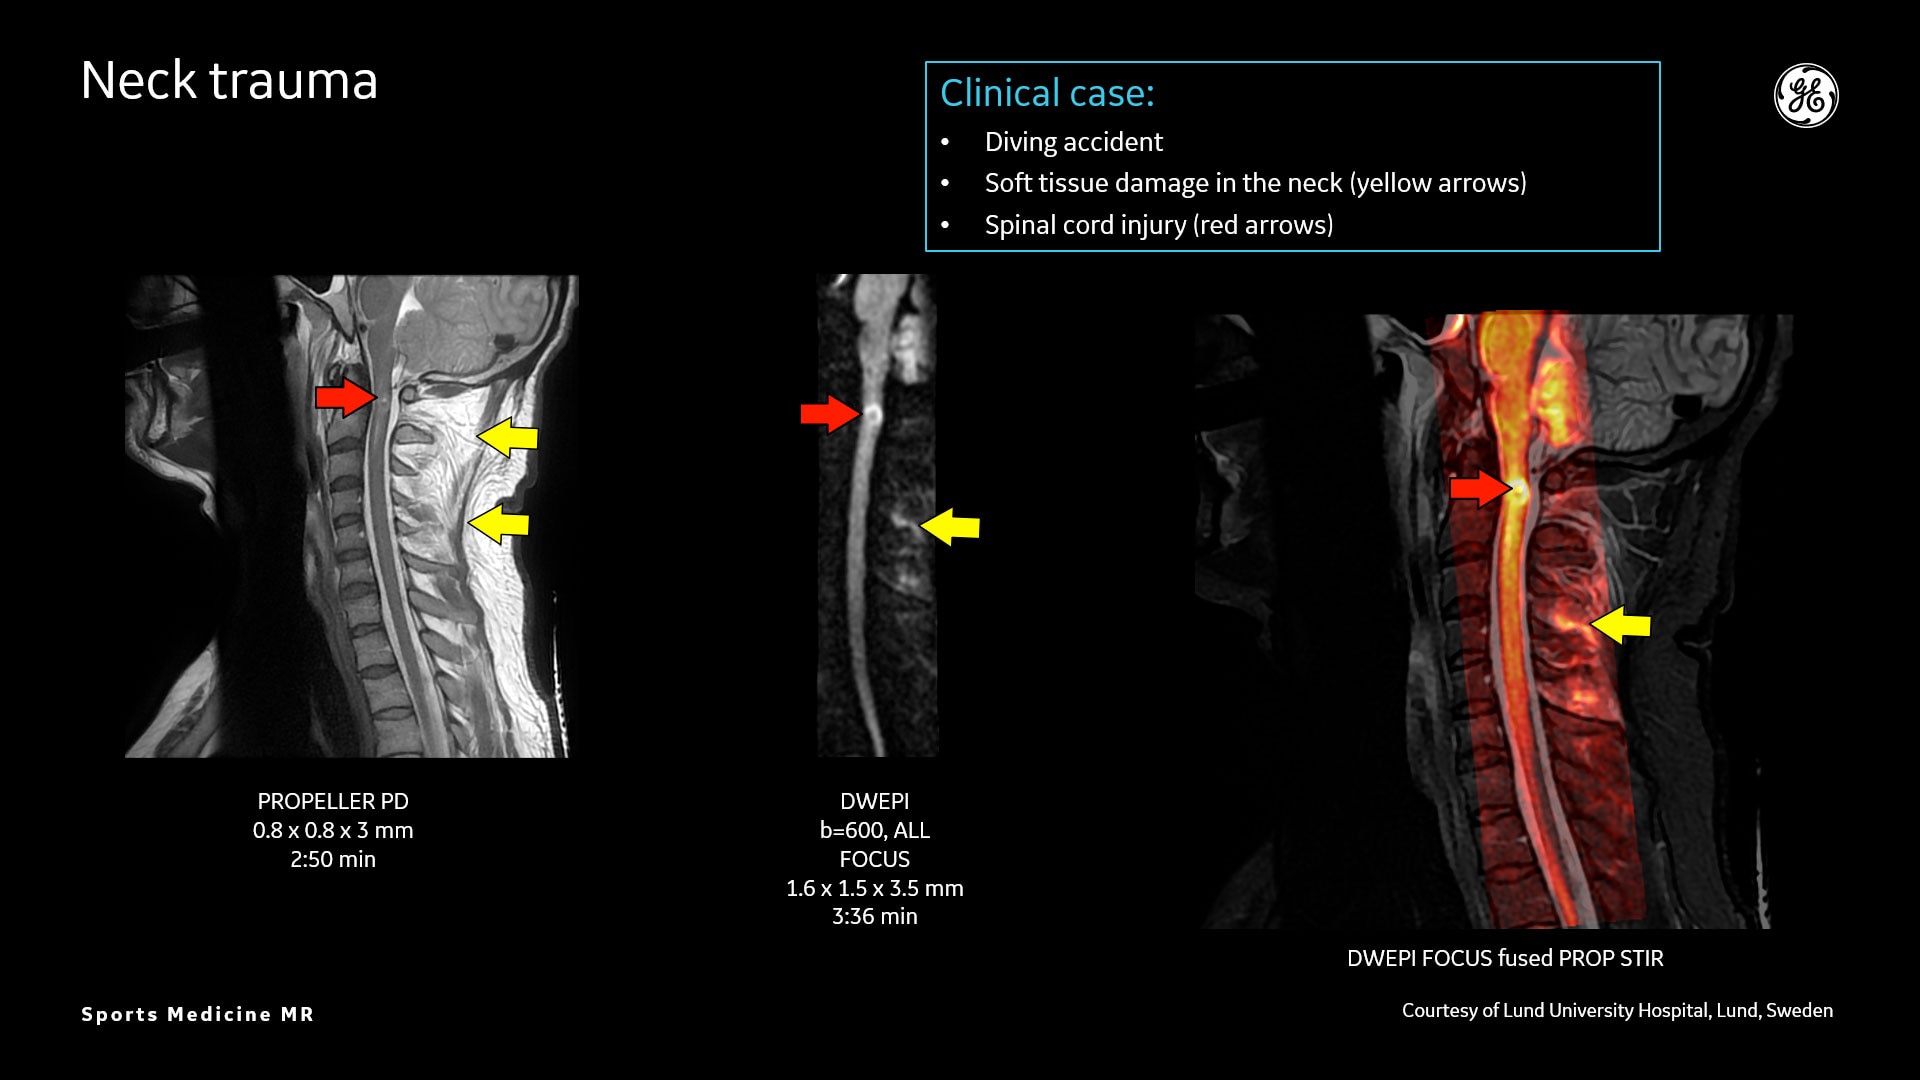

AIR™ Recon DL liefert hochauflösende Bilder mit erhöhtem SNR bei deutlich reduzierten Scanzeiten. Diese Technologie optimiert die Darstellung selbst kleiner Verletzungen wie Meniskus-, Labrum- und Bänderrisse. Die Verkürzung der Scanzeiten erhöht die Flexibilität für individuell abgestimmte MR-Protokolle mit einer zusätzlichen oZTEo-Sequenz für eine detaillierte Frakturbeurteilung.